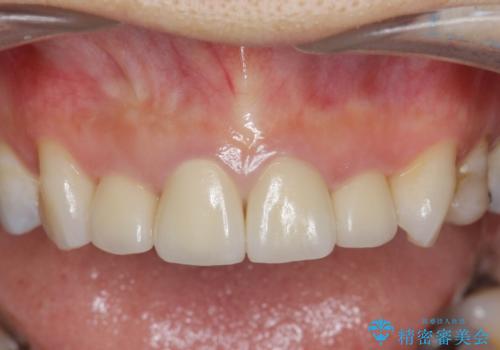

自然で美しい前歯の仕上がりとなり、大変満足していただくことができました。